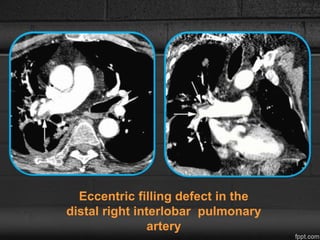

• Organizing thrombi - Eccentric filling defects adjacent to the

vessel wall

• Organizing thrombi with recanalization - small foci of contrast

within an

• occluded vessel.

Eccentric filling defect in the

distal right interlobar pulmonary

artery

Imaging Manifestations CXR • Initiallynormal, but later the enlargement of the main, right, and left pulmonary arteries are evident. • Subpleural opacities - recent or remote pulmonary infarction. CTPA • Organizing thrombi - Eccentric filling defects adjacent to the vessel wall • Organizing thrombi with recanalization - small foci of contrast within an • occluded vessel. • Intravascular webs- Linear intraluminal filling defects. • Abrupt narrowing of pulmonary arteries with reduction in arterial

Eccentric filling defectin the distal right interlobar pulmonary artery